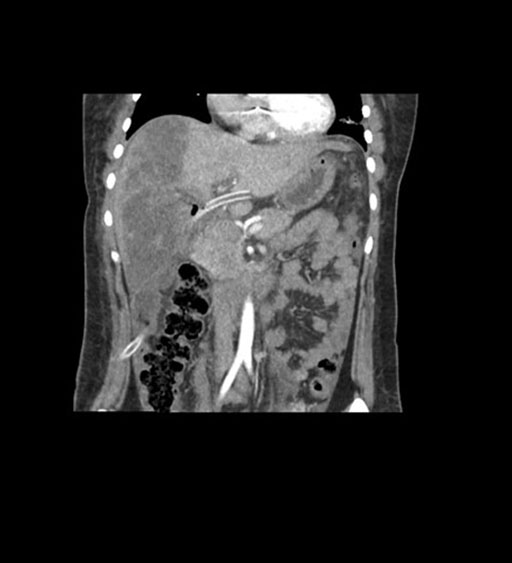

Coronal Arterial